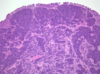

What type of cancer is seen here?

• KEY Features?

• what would you expect to see on microscopic examination?

Renal Clear Cell Carcinoma

• Key Features

• solitary, well defined, polar

• YELLOW, cysts , necrosis, HEMORRHAGE

MICROSCOPIC FEATURES:

• Clear LIPID FILLED cells with CHICKEN WIRE vessel formation found between the cells